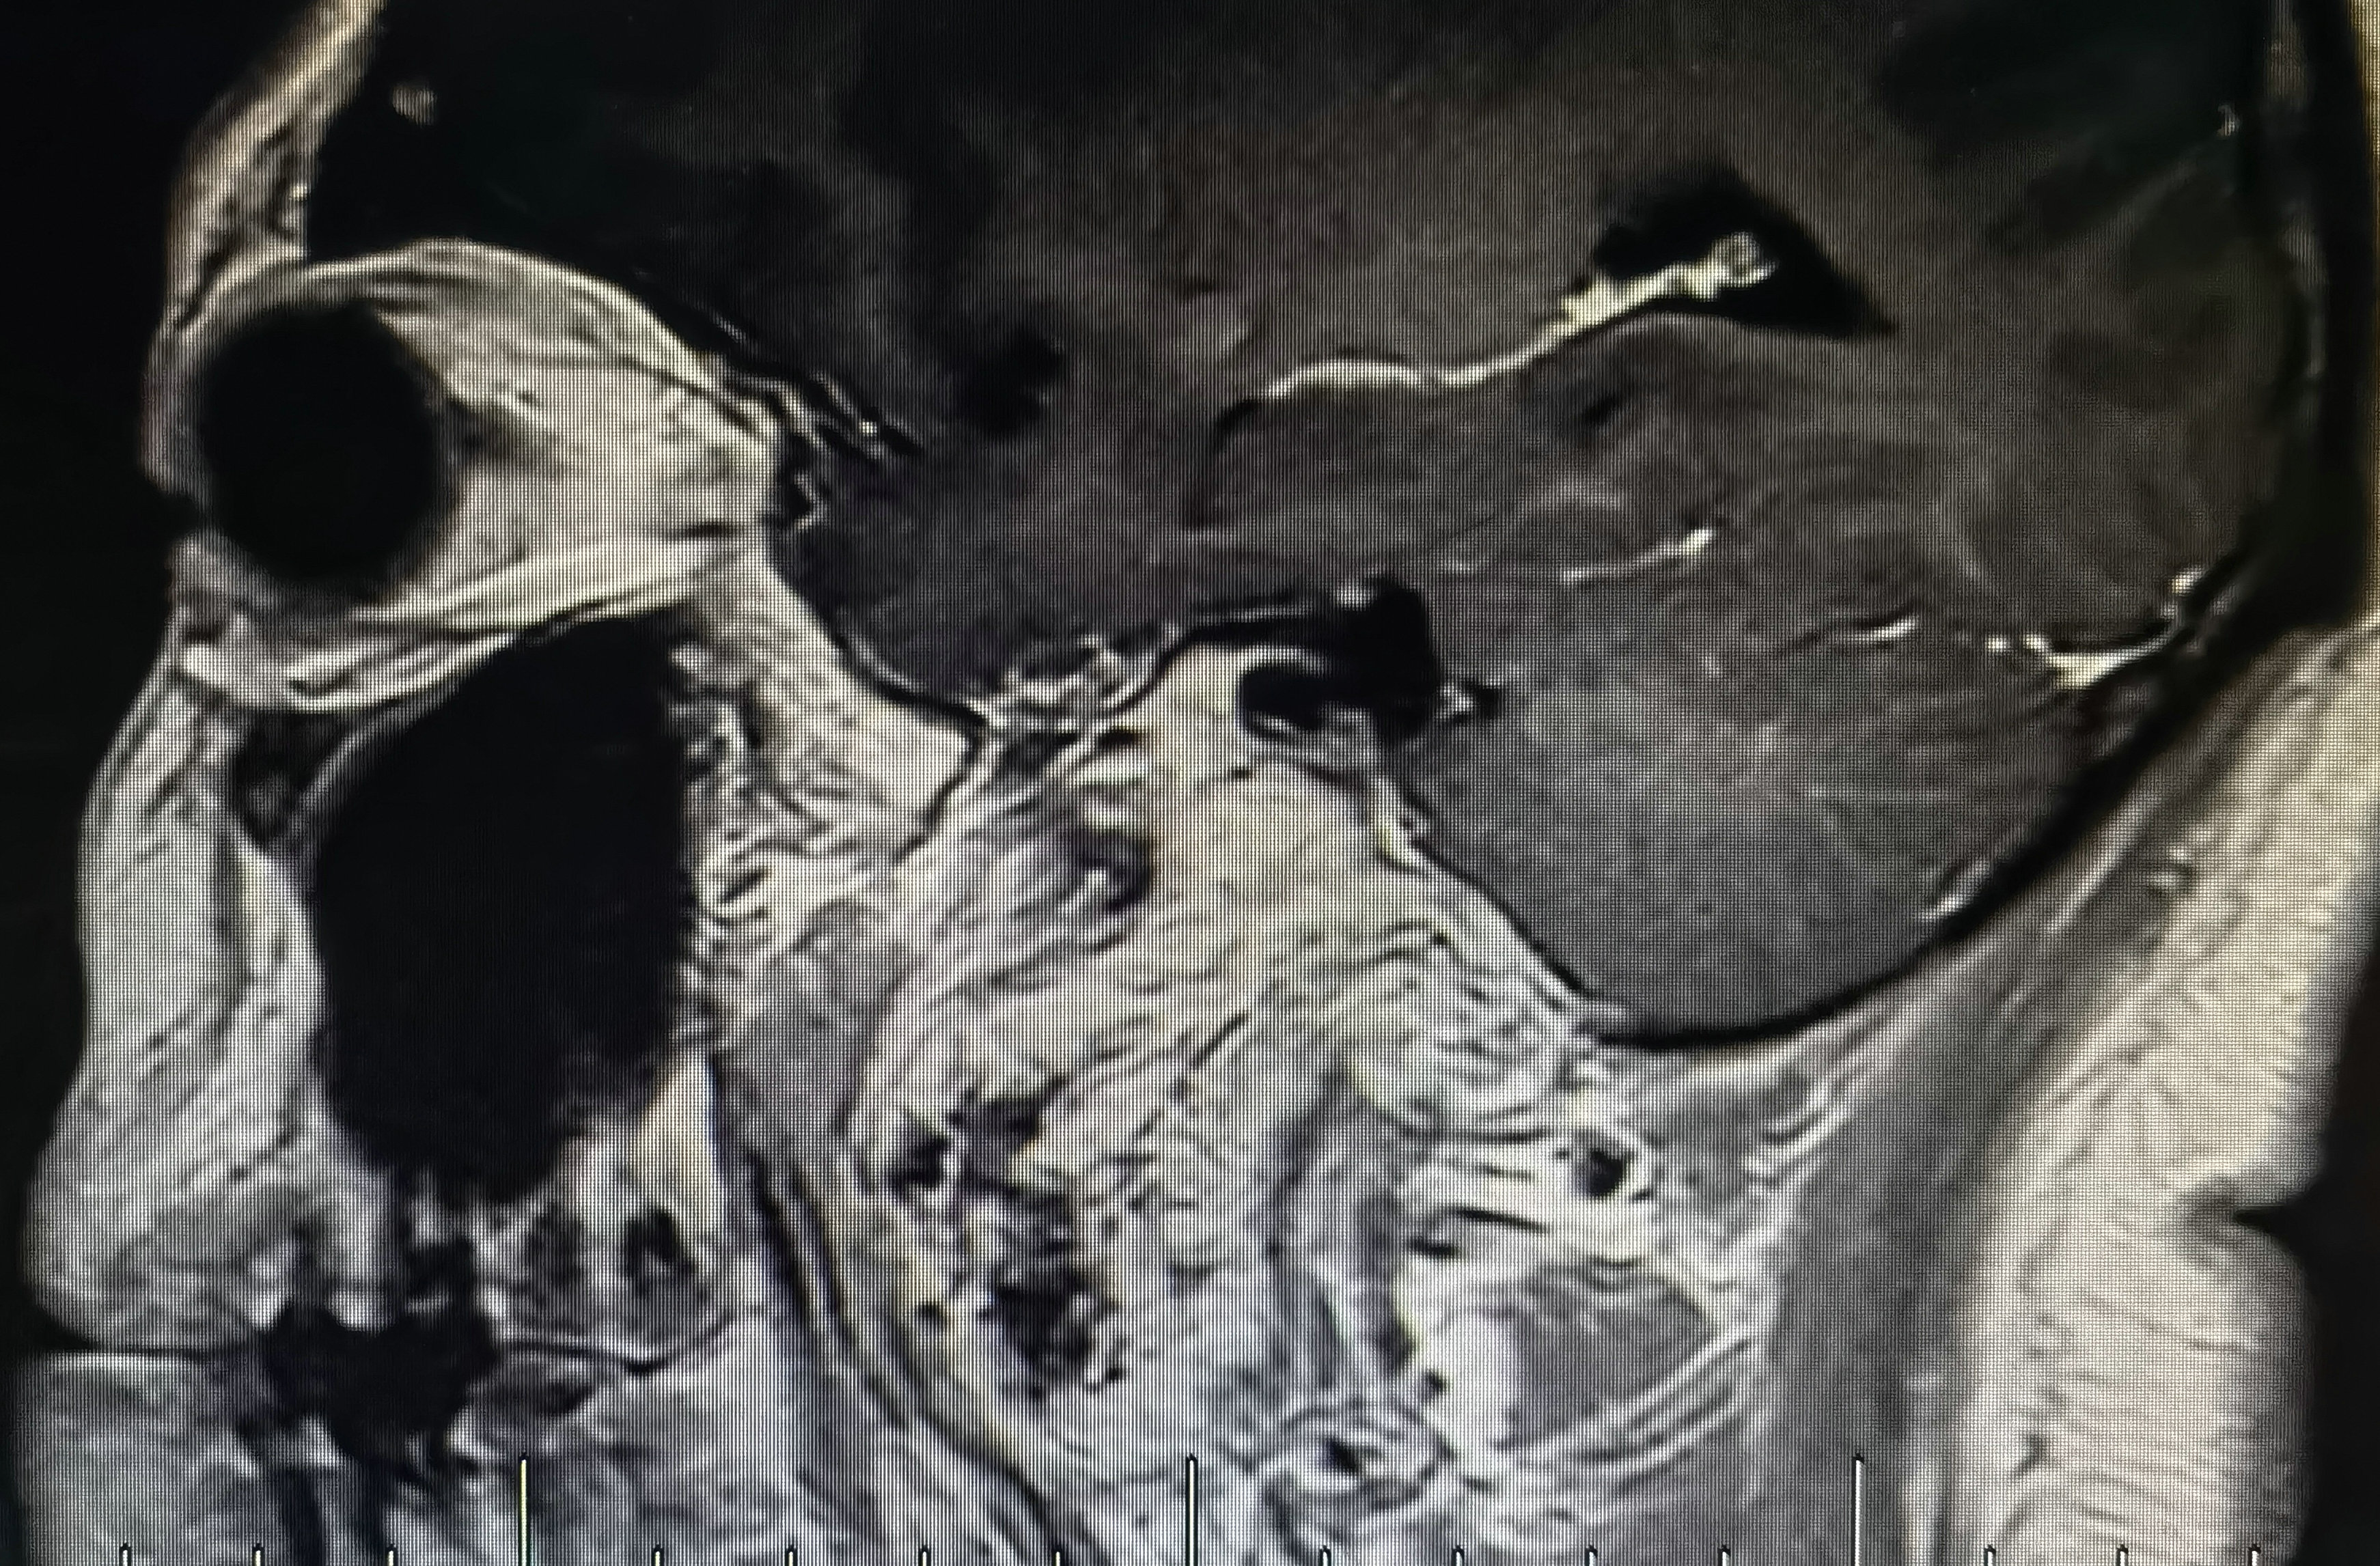

术前磁共振